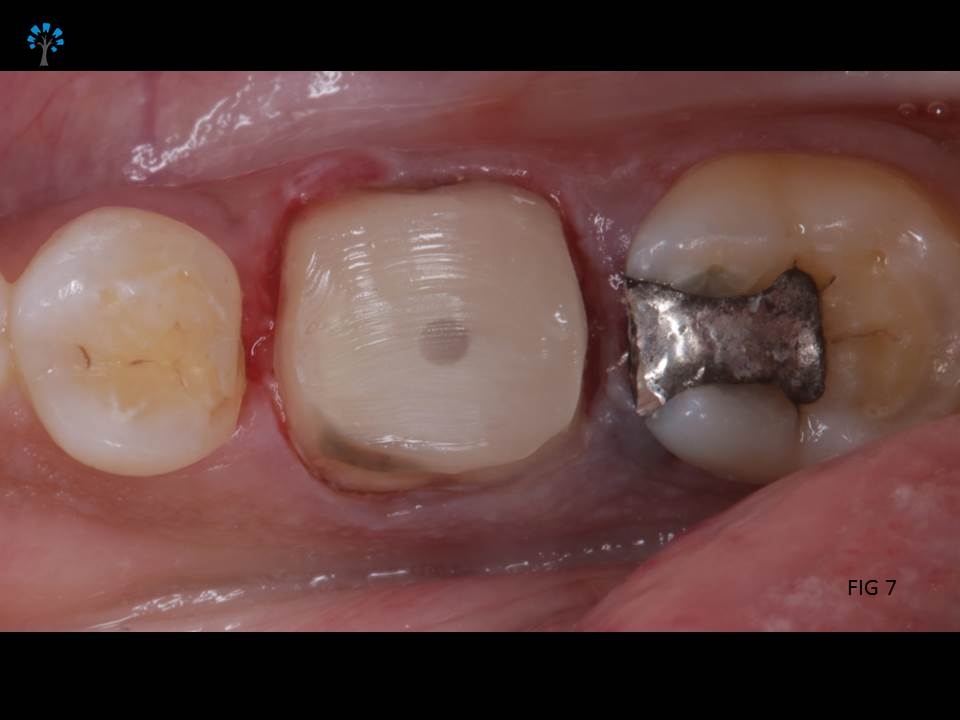

Next step was to build a core structure (Fig 6 shows isolation), in order to place a crown or a cap.

Fiber Post (IVOCLAR*) was placed and the core structure was built.(Fig 7 – 9)